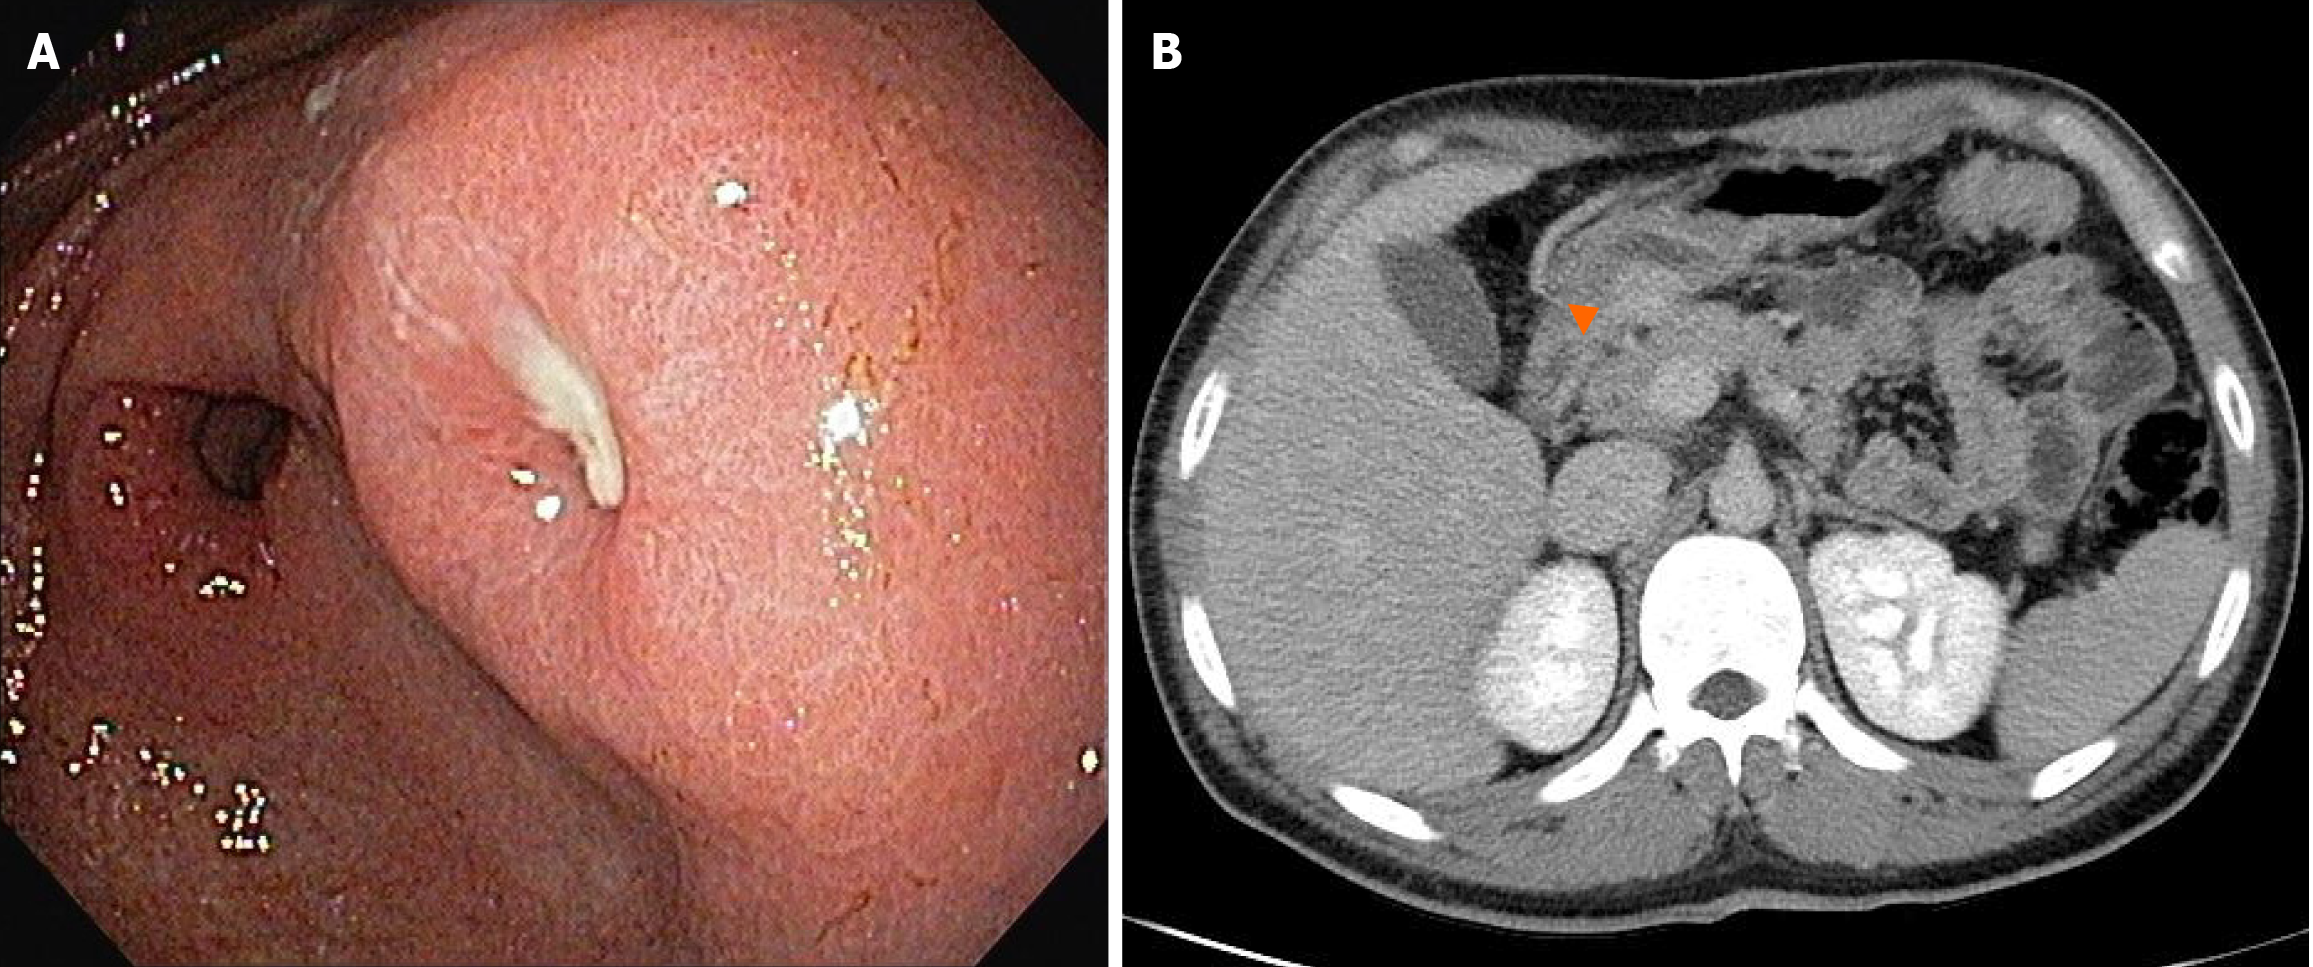

Figure 1 Endoscopy and abdominal computed tomography findings.

A: Endoscopic image showing a protruding lesion with central ulceration on the posterior wall of the distal gastric antrum; B: Axial contrast-enhanced computed tomography image showing a well-defined, hypervascular subepithelial lesion (orange arrowhead) along the posterior wall of the distal gastric antrum.